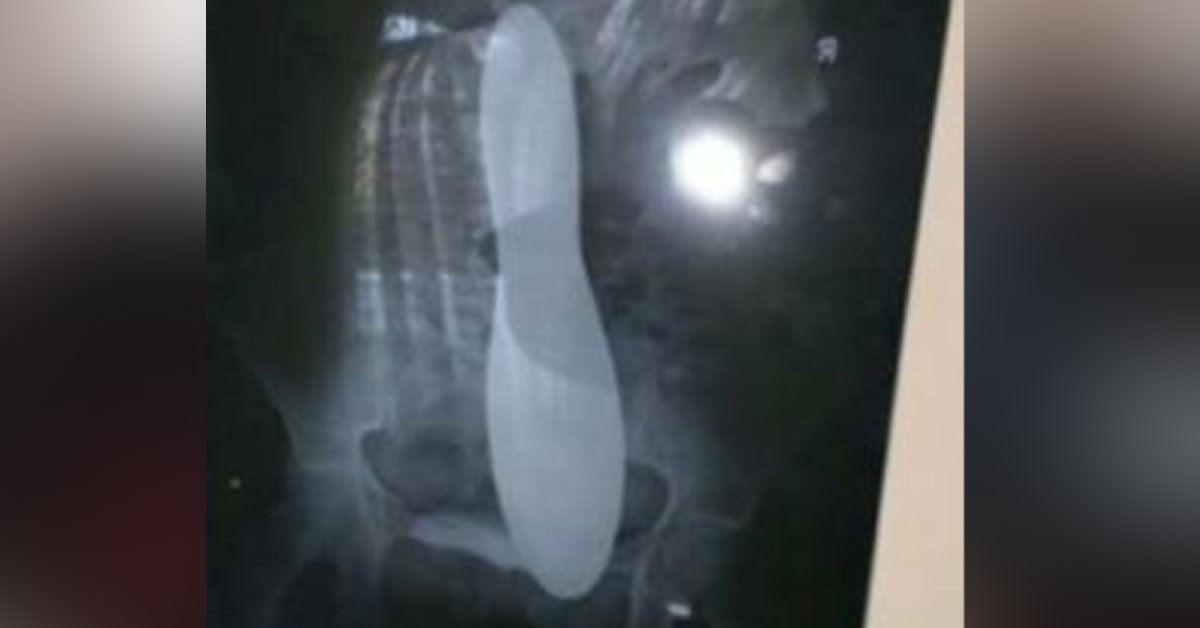

Fatma Soylu'ya hastanede doktorlar ameliyat sonrası ağrıların normal olduğunu söyleyip geri gönderdi. Fatma Soylu 42 gün boyunca ağrılara dayanmaya çalıştı. Fatma Soylu, şiddetlenen ağrıların yanı sıra nefes alma problemi yaşamaya başlayınca tekrar hastaneye gitti. Fatma Soylu'ya bu sefer ultrason çekildi. Çekilen ultrasonda Fatma Soylu'nun karnında metal bir cisme rastlandı. Fatma Soylu'nun geçirdiği ameliyatı sırasında doktorların karnında metal cismi unuttuğu anlaşıldı.

Ameliyat sırasında doktorların karında unuttuğu mala tekrar yapılan ameliyatla çıkartıldı. Fatma Soylu, yaşanan durumun ardından İstanbul Haseki Eğitim ve Araştırma Hastanesi'ne ve ameliyatını yapan sağlık ekibine dava açtı. İstanbul 7. İdare Mahkemesi kusuru Sağlık Bakanlığı'nda sayarak Fatma Soylu'ya 82 bin 71 lira tazminat ödenmesine hükmetti. Sağlık Bakanlığı parayı ödedi ancak Sağlık Bakanlığı tazminatı geri almak için ameliyatı yapan doktor ve hemşireye dava açtı. Ameliyatta kullanılan araçların hemşire tarafından tek tek sayılması ve hem hekim hem de ameliyat hemşiresi tarafından bu sayımın tutanağa bağlanması gerektiğini belirten Sağlık Bakanlığı, Fatma Soylu'ya ödenen tazminatın doktor ve hemşireden tahsil edilmesini istedi.

Genç kadına ultrason çekildi. Çekilen ultrasonda metal bir cisim fark edildi.

Fatma Soylu'nun ameliyat sırasında karnında mala unutulduğu tespit edildi.